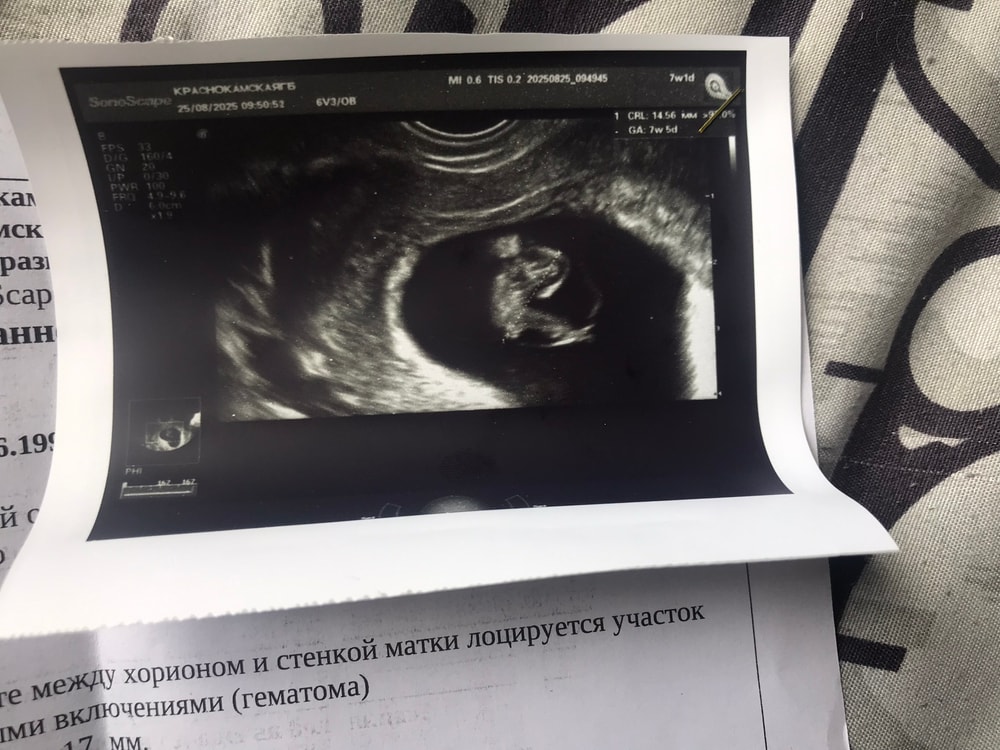

Гематома и деформация плодного яйца

Девочки кто сталкивался с таким ? Нормально ли все прошло ? Ребёнок здоровый родился ? Врач сказала что возможно будут патологие у ребёнка. Были выделения из за гематомы щас все прекратилось, живот не болит не чего все хорошо, не знаю что делать, врач говорит аборт лучше сделать, срок уже почти 9 недель, по узи все 10 недель

Какой аборт? Беременность развивается. Сердцебиение есть. Вам нужен более компетентный врач. Гематома вкупе с деформацией пя -это возможная угроза выкидыша. Если беременность желанная, ее можно сохранить, нужно обратиться к другому врачу и он назначит поддержку.